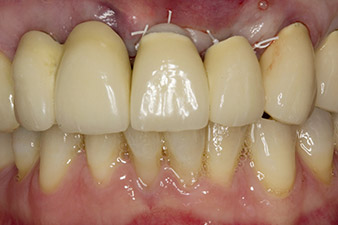

Situation following implantation

Fig. 6: Situation following implantation and augmentation: The old bridge was reinserted as a temporary restoration for the healing phase with a freely milled pontic at implant position 22. The planned permanent restoration will be a zirconium oxide bridge from 12 to the implant yet to be inserted at position 23.

In order to compensate for the periodontal bone loss and achieve an aesthetically pleasing result, the implantation was combined with guided bone regeneration (GBR) with xenogenic replacement material and a collagen membrane

(Fig. 5 and 6).